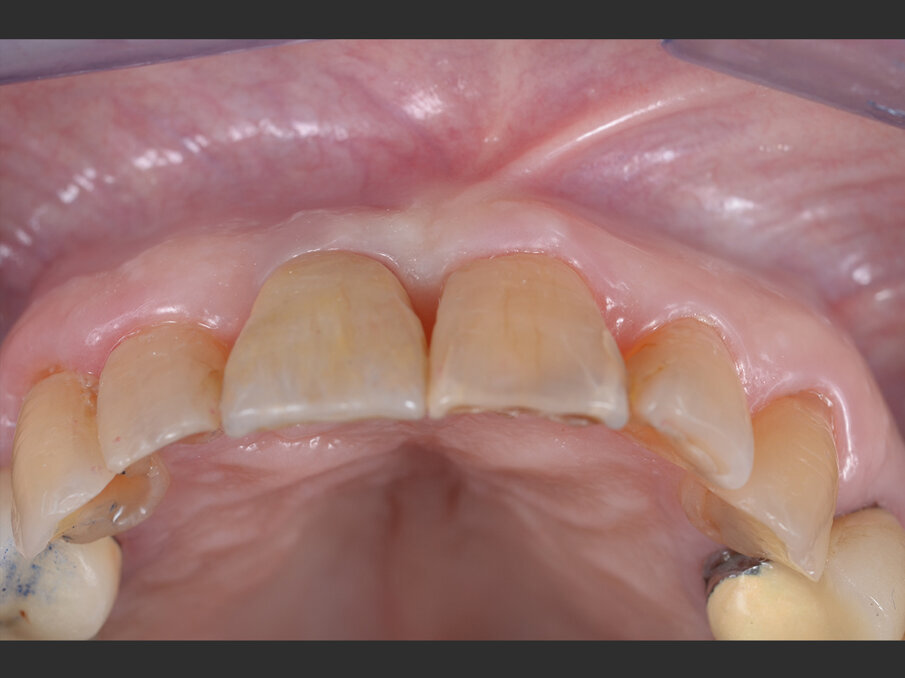

Un moncone in titanio per protesizzazione provvisoria (componente secondaria provvisoria - Straumann) viene modificato così da permettere un corretto alloggiamento della corona provvisoria e serrato manualmente. Protetto il canale della vite, il provvisorio viene forato in corrispondenza dell’accesso della vite protesica, posizionato in sede grazie alle alette e bloccato utilizzando del composito flow (G-aenial Universal flo - GC). Rimossa dal cavo orale, la corona provvisoria viene rifinita in laboratorio, completando il tragitto transmucoso in composito (Essentia Universal - GC) in modo tale da modellare un’area sotto-gengivale che sostenga i tessuti senza comprimerli. La riabilitazione provvisoria viene posizionata, avvitata e serrata a 20 N/cm. Il foro di accesso viene protetto con PTFE e sigillato con un’otturazione provvisoria (Telio CS onlay - Ivoclar), e i contatti occlusali vengono scaricati in modo tale da eliminare interferenze occlusali (Figg. 5, 6). Viene prescritta terapia farmacologica antibiotica, antidolorifica e sciacqui con collutorio a base di clorexidina digluconato. La paziente viene controllata a 7 giorni, 45 giorni e 90 giorni. A distanza di 3 mesi l’impianto viene considerato osteointegrato e i tessuti molli hanno raggiunto la loro stabilità. Il provvisorio viene quindi svitato (Fig. 7) e si procede tramite impronta ottica (Trios 3 - 3Shape) al trasferimento in laboratorio della posizione tridimensionale dell’impianto, della morfologia del tragitto transmucoso e della morfologia della componente sottogengivale della corona provvisoria (Figg. 8a, 9b). Una corona avvitata in zirconia con microstratificazione vestibolare viene confezionata come riabilitazione definitiva (Fig. 10). Superata la prova estetica, il manufatto viene consegnato e serrato a 35 N/cm. Il foro passante viene sigillato con PTFE e resina composita (G-aenial - GC) (Figg. 11, 12).

Fig. 7 - Valutazione clinica a 3 mesi dal posizionamento: l’impianto è ben integrato ed i tessuti molli sono stabili.